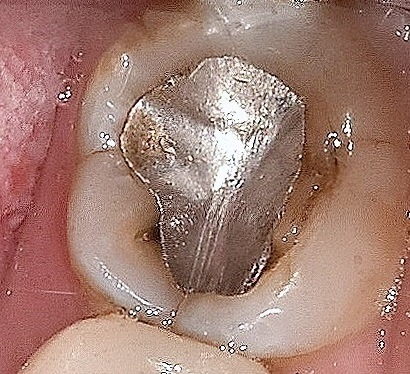

아말감 치료 후 오랜 시간이 경과한 치아 예시

이 중 아말감은 수은과 다른 물질을 섞어서 만들게 되는데요.

굳기 전에 충치를 제거한 부분에 다져넣으면 서서히 단단해지면서 굳게 됩니다.

치료비용이 저렴하기는 하지만 수은을 사용하기 때문에 인체 유해성 논란이 있기도 하고,

아말감과 치아의 틈새로 세균이 침투해 2차 충치가 발생할 가능성이 높다는 점,

색상이 굉장히 예쁘지 않은 금속 색상이기 때문에 심미적인 문제로 인해 요즘에는 사용 빈도가 많이 줄어들었죠.